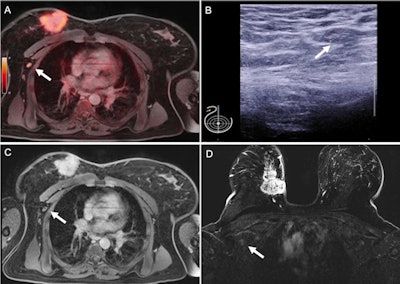

Pathologically confirmed axillary lymph node metastasis that was correctly identified on F-18 FDG PET/MRI (A) because of tracer uptake above background levels (SUVmax 4.3) and in axillary sonography (B) because of cortical enlargement to 3.8 mm (short-axis diameter 8 mm). This lymph node was rated unsuspicious on thoracic MRI (C) and breast MRI (C). Large primary cancer is seen in the right breast (D). Figure courtesy of Journal of Nuclear Medicine.Histopathology served as a reference standard in every patient, while area under the receiver operating characteristic curve (AUC) values were used to measure performance. Sensitivity, specificity, positive predictive value, negative predictive value, and accuracy were calculated for all four modalities.